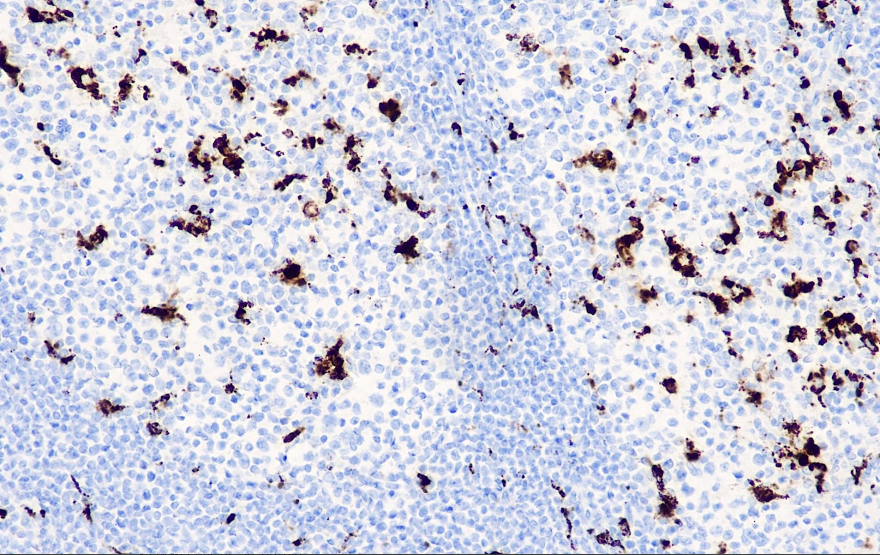

Positive control: tonsils

CD68 is a glycoprotein with a molecular weight of 110 kD that detects macrophages in human tissues, including Kupffer cells and macrophages in the spleen, intestinal lamina propria, alveoli, and bone marrow, and also labels bone marrow precursor cells and peripheral blood granulocytes and monocytes.

CD68 Antibody Reagent binds specifically to CD68 molecular antigen. Immunohistochemistry kits containing CD68 Antibody Reagent are indicated for the precise diagnosis of myelomonocytic and histiocytomas.